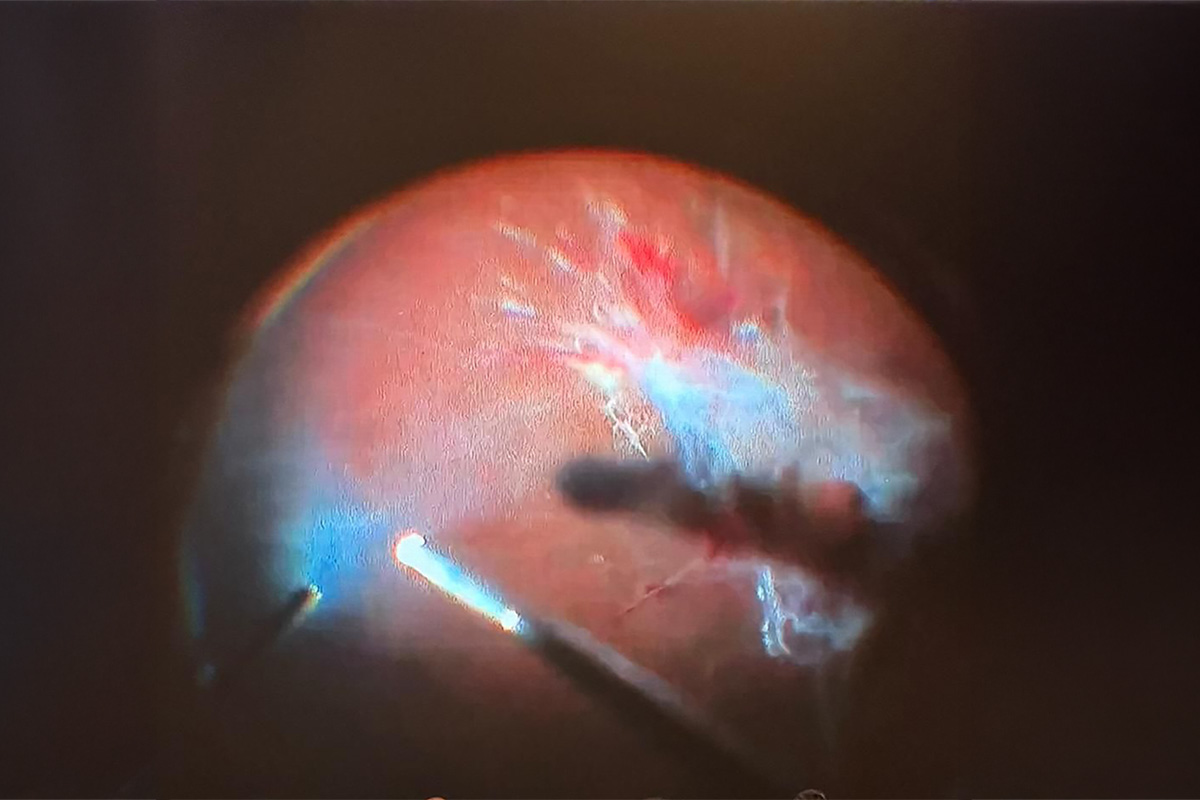

I shared my knowledge with my colleagues as a speaker at the session on Approaches to Challenging Vitreoretinal Surgery Cases at the TOD National Congress. I explained the critical points in two challenging vitrectomy (vitreoretinal surgery) cases I performed to my ophthalmologist colleagues.